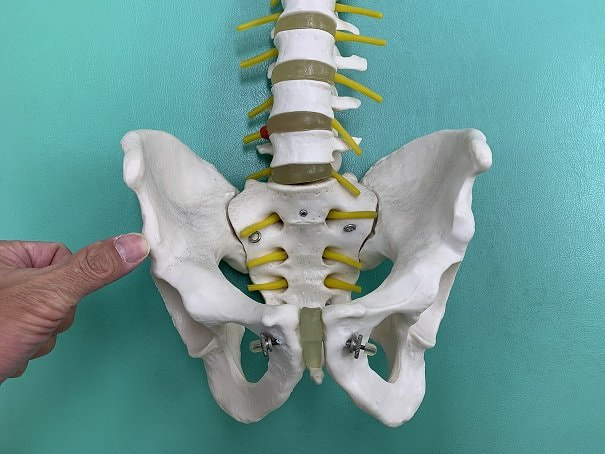

下前腸骨棘付近損傷.jpg

「下前腸骨棘剥離骨折」とは、骨盤前面の腸骨という骨の出っ張りには、

上前腸骨棘と下前腸骨棘と呼ばれる突起があります。

下前腸骨棘.jpg

上前腸骨棘には大腿筋膜張筋・縫工筋、下前腸骨棘には大腿直筋という、

ジャンプ動作、ボールを蹴る動作時に作用する筋肉が付着しており、

急な動作の繰返し、急激な収縮作用による牽引力によって、筋肉の付着部が炎症を起したり、

上前腸骨棘、下前腸骨棘部が剥離骨折を起こすスポーツ障害です。